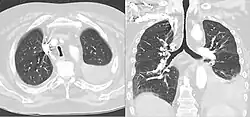

CT scan of a saber-sheath trachea in a patient with COPD

A saber-sheath trachea also known as scabbard trachea is a trachea that has an abnormal shape. This manifests as a narrowing of the portion of the trachea located within the thorax, and a widening of the diameter of the posterior area of the trachea. The lateral measurement of tracheal diameter decreases. In saber-sheath trachea, the inner wall of the trachea is smooth, there are no nodules or areas of thickening.

On typical CT scans of the trachea, the normal appearance is oval, round, or horseshoe shaped. A saber-sheath trachea has distinct findings compared to normal tracheas on imaging, and may have additional features on CT besides intra-thoracic narrowing and widening diameter of the posterior portion. When cartilage becomes weak, as in saber-sheath trachea, CT scans can show the sides of the trachea curving inwards. This can be more apparent with forceful exhalation Moreover, the walls of the trachea within the thorax can also show slight thickening on CT. Another finding that can be seen is the hardening and becoming more bone-like of the cartilaginous rings in the trachea, a process called ossification.[5]